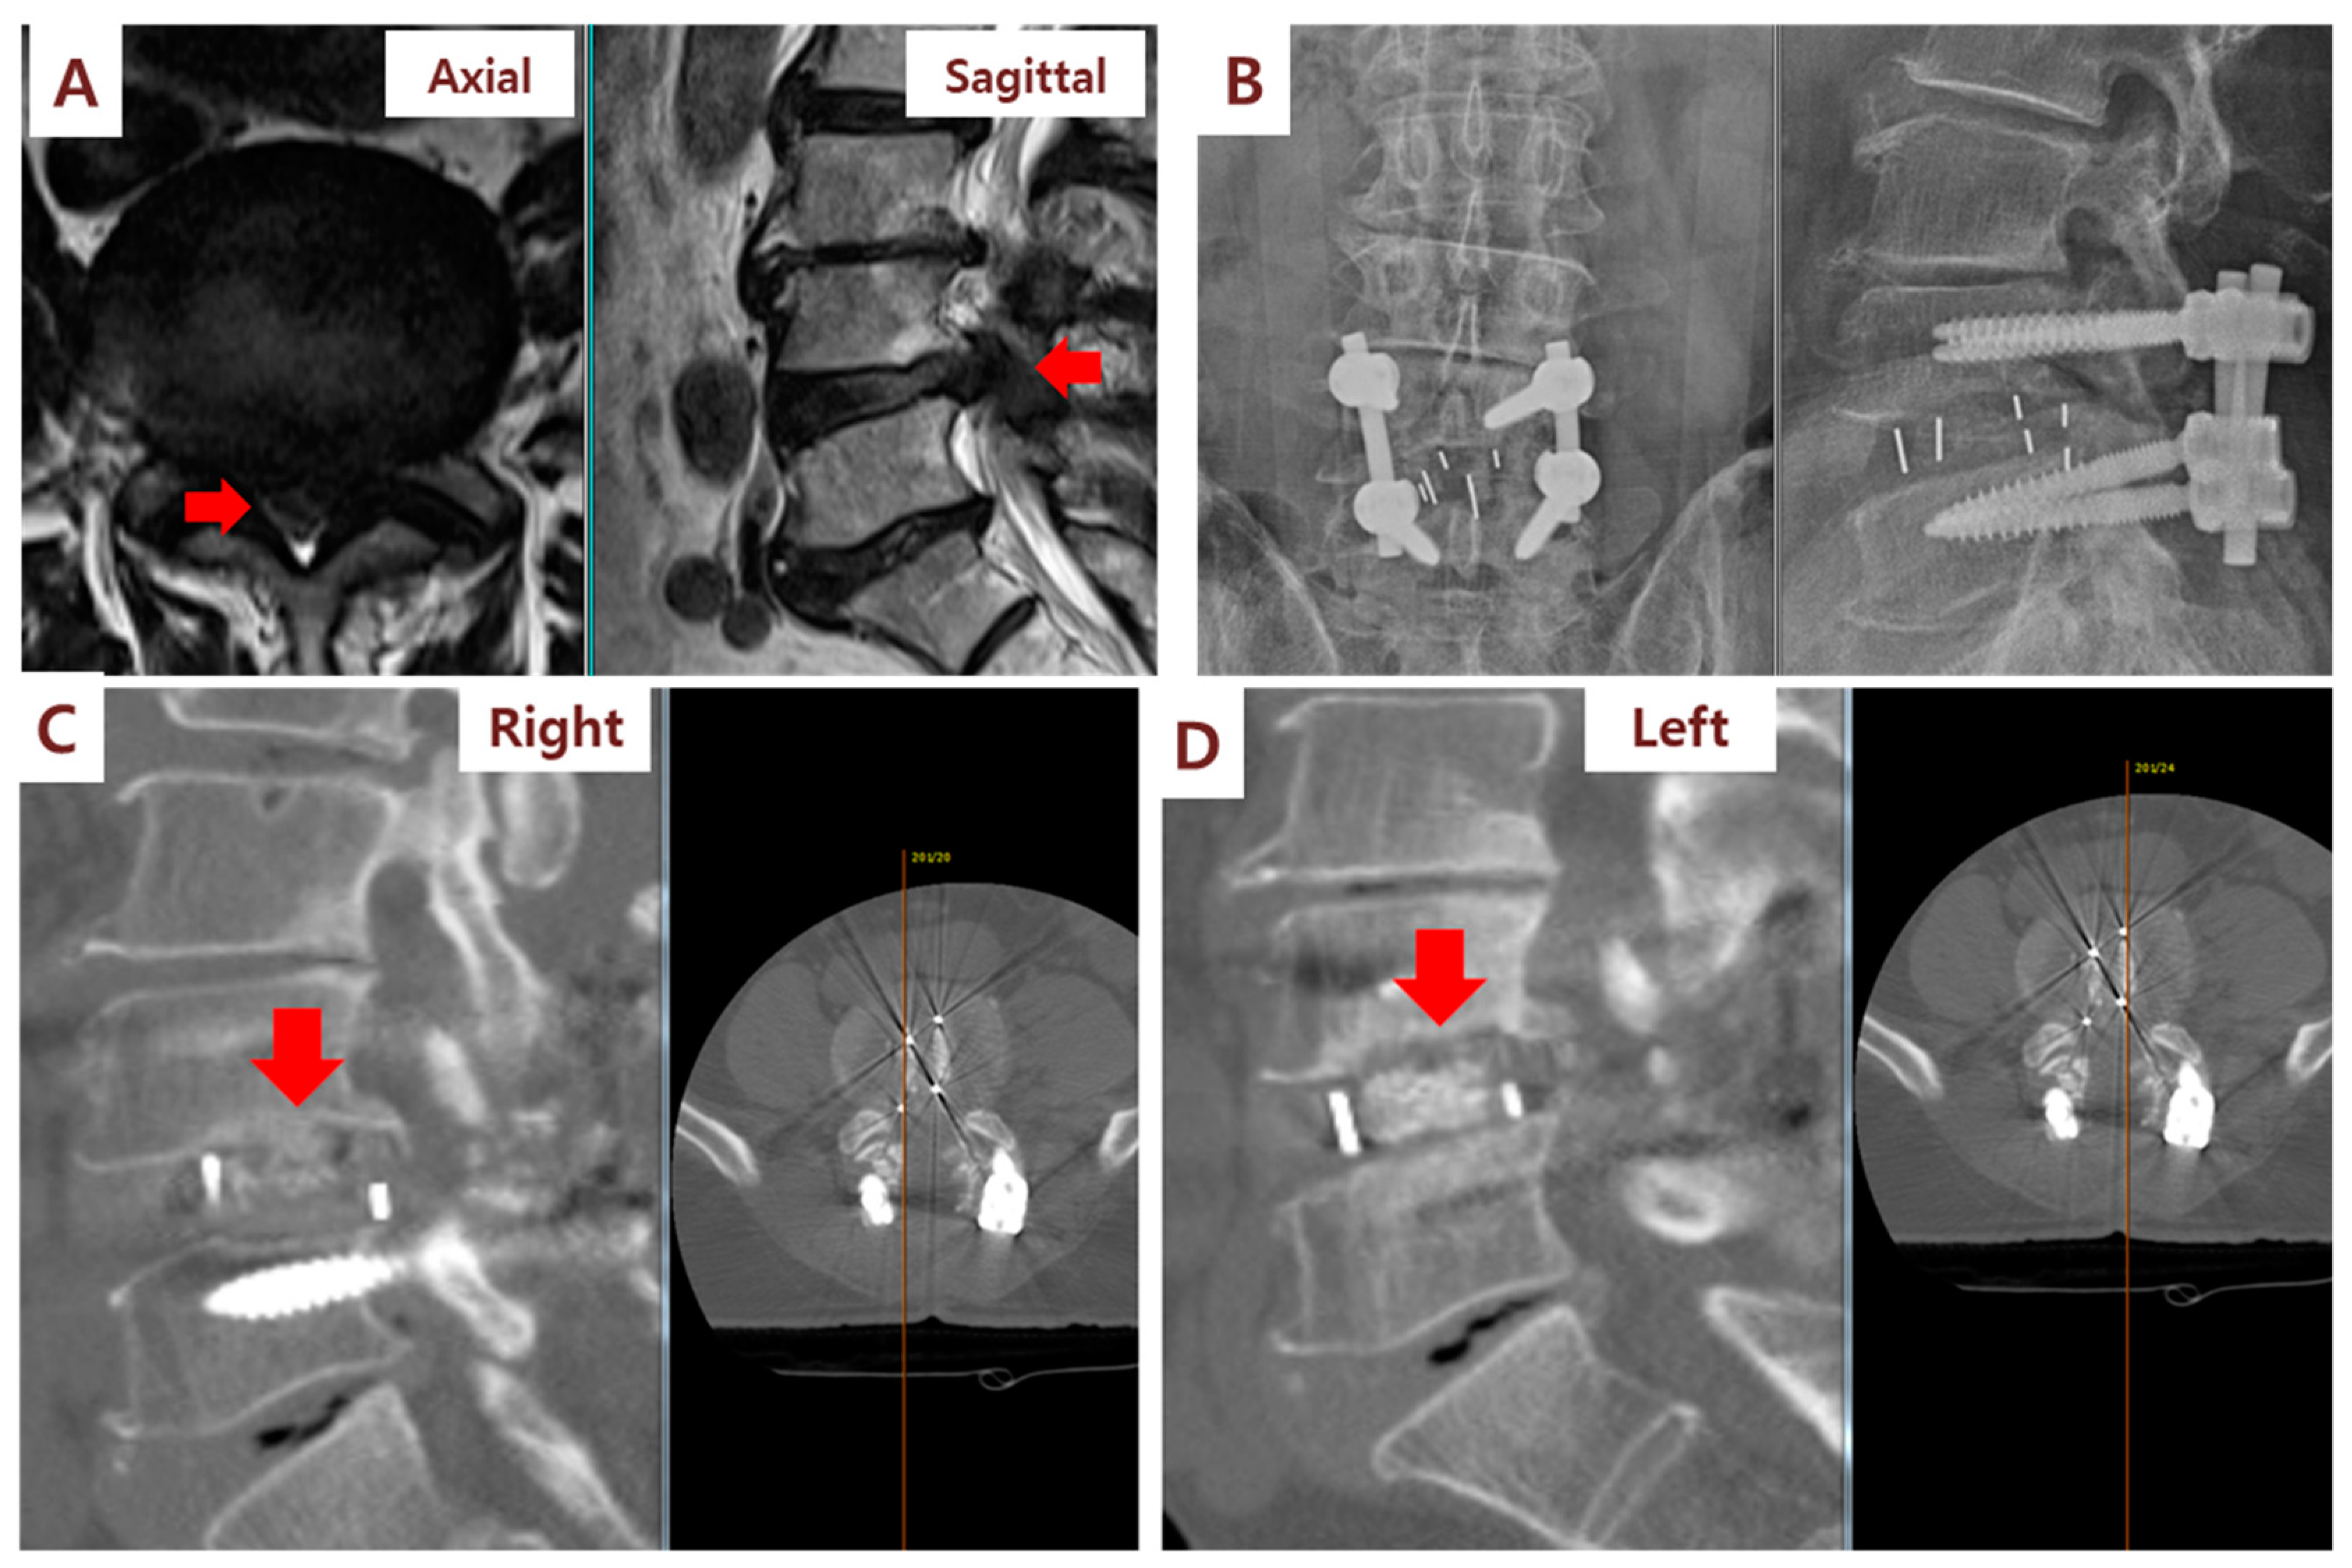

Figure 4.

Illustration case (Patient No. 3): A 67-year-old male received posterior lumbar interbody fusion and pedicle screw fixation. (A) Preoperative lumbar axial and sagittal MRI demonstrating L4/L5 severe spinal stenosis. (B) Postoperative lumbar spine standing anteroposterior and lateral view. (C) CT sagittal view at 6 months after surgery showed fusion status (red arrow) of cages filled with SVF and β-TCP mixture on the right side of the patient. (D) By contrast, CT sagittal view showed no fusion status (red arrow) of cages filled with β-TCP alone on the left side.